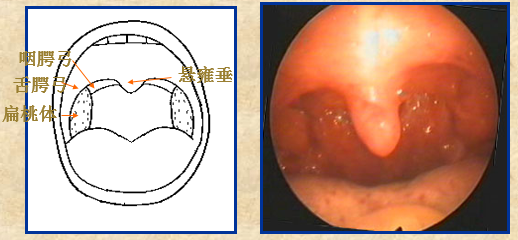

3、正常口咽部

耳鼻喉头灯怎么用实用干货!耳鼻咽喉的检查方法,你都掌握了吗?_https://www.jmylbn.com_新闻资讯_第23张

急性化脓性扁桃体炎:右扁桃体充血肿胀,有脓性分泌物。

耳鼻喉头灯怎么用实用干货!耳鼻咽喉的检查方法,你都掌握了吗?_https://www.jmylbn.com_新闻资讯_第24张

扁桃体周围脓肿:左侧咽腭弓及扁桃体充血肿胀,有脓性分泌物附着。

耳鼻喉头灯怎么用实用干货!耳鼻咽喉的检查方法,你都掌握了吗?_https://www.jmylbn.com_新闻资讯_第25张